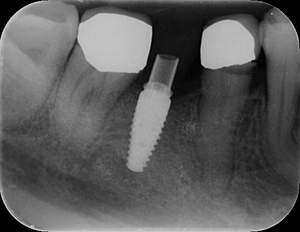

レントゲン写真

- Befor

- After

| 年齢 | 50代・男性 |

| 主訴 | 左下7番 |

| 治療内容 | 右下7番インプラント埋入 |

| 治療費 | 合計:572,000円 診断料:55,000円 埋入料:165,000円 サージカルガイド:55,000円 静脈内鎮静麻酔:77,000円 仮歯:55,000円 上部構造(フルジルコニア):165,000円 (2023年1月現在) |

| 治療期間 | 約8ヶ月 |

| 治療方針 | 骨が十分にあるため、骨造成をすることなく埋入した。かみ合わせが強いので、負荷がかからないよう、夜寝るときにマウスピースをつけるよう指示をした。 |

| 担当者所見 | 左下6番7番のインプラントは他院で埋入しており、右下7番は抜歯したままで、かみ合わせの歯が落ちてきてしまうのでインプラントを埋入しました。 |